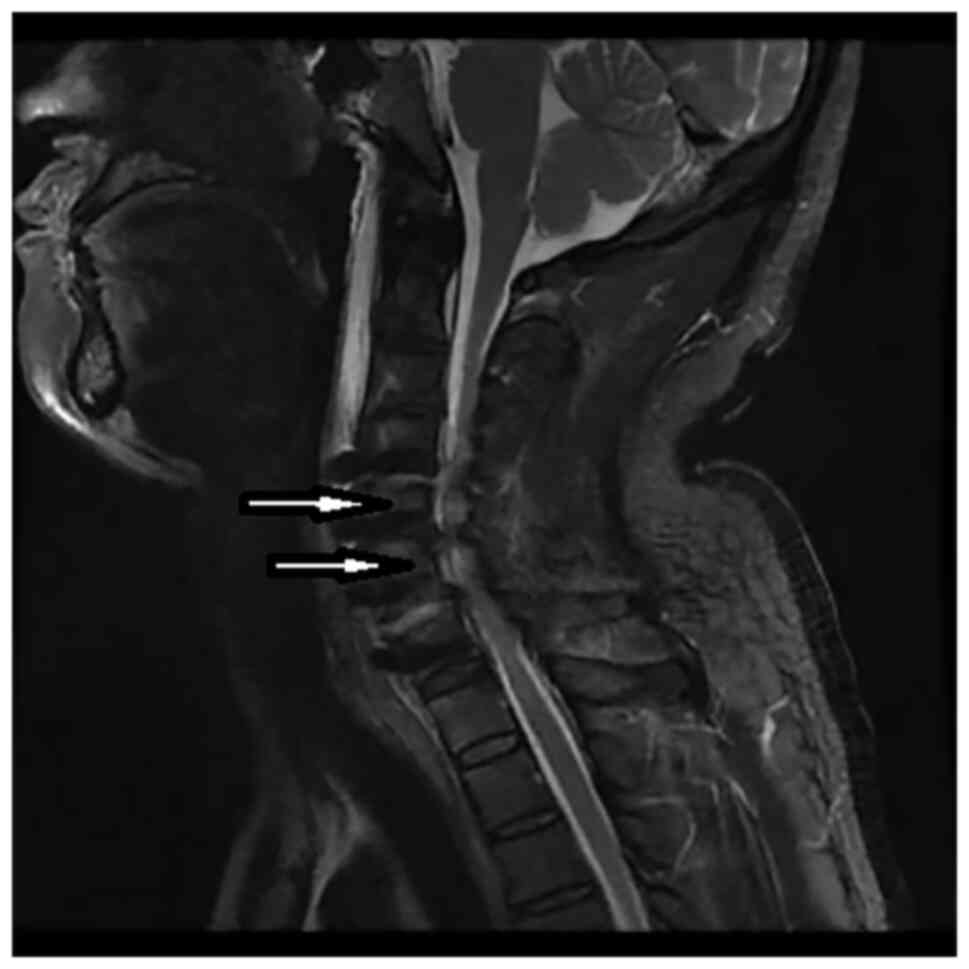

A 54-year-old man was admitted to Jinhua Municipal Central Hospital (Jinhua, China) in March 2021 with complaints of numbness and weakness in limbs and swelling in the neck. His myelopathic neurological examinations were negative. Physical examination determined that the strength in his limbs was normal. The preoperative cervical MRI scan showed degeneration and herniation of the C4-C7 discs (Fig. 1). He was diagnosed with CSM. Following routine preoperative preparation, ACCF C4-C7 surgery was performed. The cord was decompressed by removing the C4-7 disc material. The interbody cages were inserted into the C4-7 disc space and the plate was fixed on the C4-7 body anterior surface. X-ray imaging displayed satisfactory positioning of the pedicle screws. Following surgery, the patient's motor and sensory impairments gradually improved. However, on the 7th postoperative day, the patient was unable to move his legs and arms. Physical examination revealed upper limb strength of 3/5 and leg strength of 3/5 according to the Medical Research Council scale (7). Emergency MRI demonstrated T2 high intramedullary signal at C5-C6 level (Fig. 2). He was diagnosed with WCS and high dose methylprednisolone (80 mg, intravenously twice/day) combined with mannitol (250 ml, intravenously twice/day) and neurotrophic drug mecobalamin (0.5 mg, orally three times/day) were administered. However, symptoms did not improve and posterior cervical decompression surgery was performed 11 days after the initial ACCF operation. The second postoperative cervical MRI scan suggested that T2 high signal intensity had faded (Fig. 3). The patient recovered well postoperatively. On day 5 post-surgery, the patient was treated with hyperbaric oxygen therapy to decrease spinal cord edema and improve reperfusion injury (8). On the 10th day after the second surgery, the patient's muscle strength in the limbs recovered to grade 4/5 and the strength in the legs recovered to grade 5/5. The patient was discharged to an inpatient rehabilitation center. The patient's neurological function had not deteriorated at the 7-month postoperative follow-up.

Figure 1

Preoperative MRI scans revealed that C4-C7 disc (white arrow) degeneration with herniation.